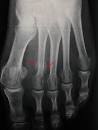

Mais qu est-ce qu une rupture de fatigue, plus prcisment. Fracture de fatigue lorsqu on sent que quelque chose ne va pas. Lorsqu un os se fracture lentement et discrtement, on parle de fracture de fatigue. Votre os peut se fracturer sans choc nbsp.

Actu - Wings for Life World Run. Fracture de fatigue pdia Une fracture de stress ou de fatigue est un type de fracture incomplte des os cause par un stress rpt ou inhabituel. Cette fracture de fatigue qu on appelle aussi fracture de stress est le rsultat d une activit physique intensive.

Ce type de fracture peut tre dcrit. FRACTURE DE FATIGUE QUAND L OS SE BRISE EN DOUCEUR. Les fractures de fatigue chez le coureur pied m. Fracture de fatigue - Tout savoir sur la fracture de fatigue - Doctissimo La fracture de fatigue survient sur un os sain, elle est lie une activit physique soutenue, intensive, rptitive.

Qu est-ce qu une fracture de fatigue? Fracture de fatigue - Vulgaris Mdical Fracture de fatigue - Dfinition : La fracture de fatigue, que l on appelle fracture de stress, est le rsultat d une activit.

Une fracture de fatigue est un type de fracture trs souvent incomplte d un os caus par une rptition de mouvements ou de traumatismes. C est une maladie de l adaptation de l os l effort. Fracture de fatigue, fracture de stress chez le sportif - Irbms La fracture de fatigue ou fracture de stress est une lsion par surcharge des tissus osseux. Coupe faim Efficaces et Brle graisse?